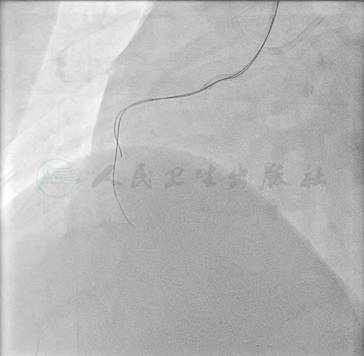

予2%利多卡因局部浸润麻醉,穿刺右侧桡动脉成功后经导丝置入6F动脉鞘。在长导引钢丝引导下,用5F TIG导管行左右冠状动脉造影,左主干未见明显狭窄,前降支近段狭窄90%伴斑块破裂征象,中远段弥漫性长病变,狭窄70%~80%,第一对角支全程狭窄40%~50%,回旋支近段管壁不规则伴扭曲,近中段完全闭塞,第一钝缘支提供侧支循环供应回旋支远端;右冠近段完全闭塞,可见少许圆锥支侧支使右冠远段显影(图1~图3)。

图1 左冠造影1

图2 左冠造影2